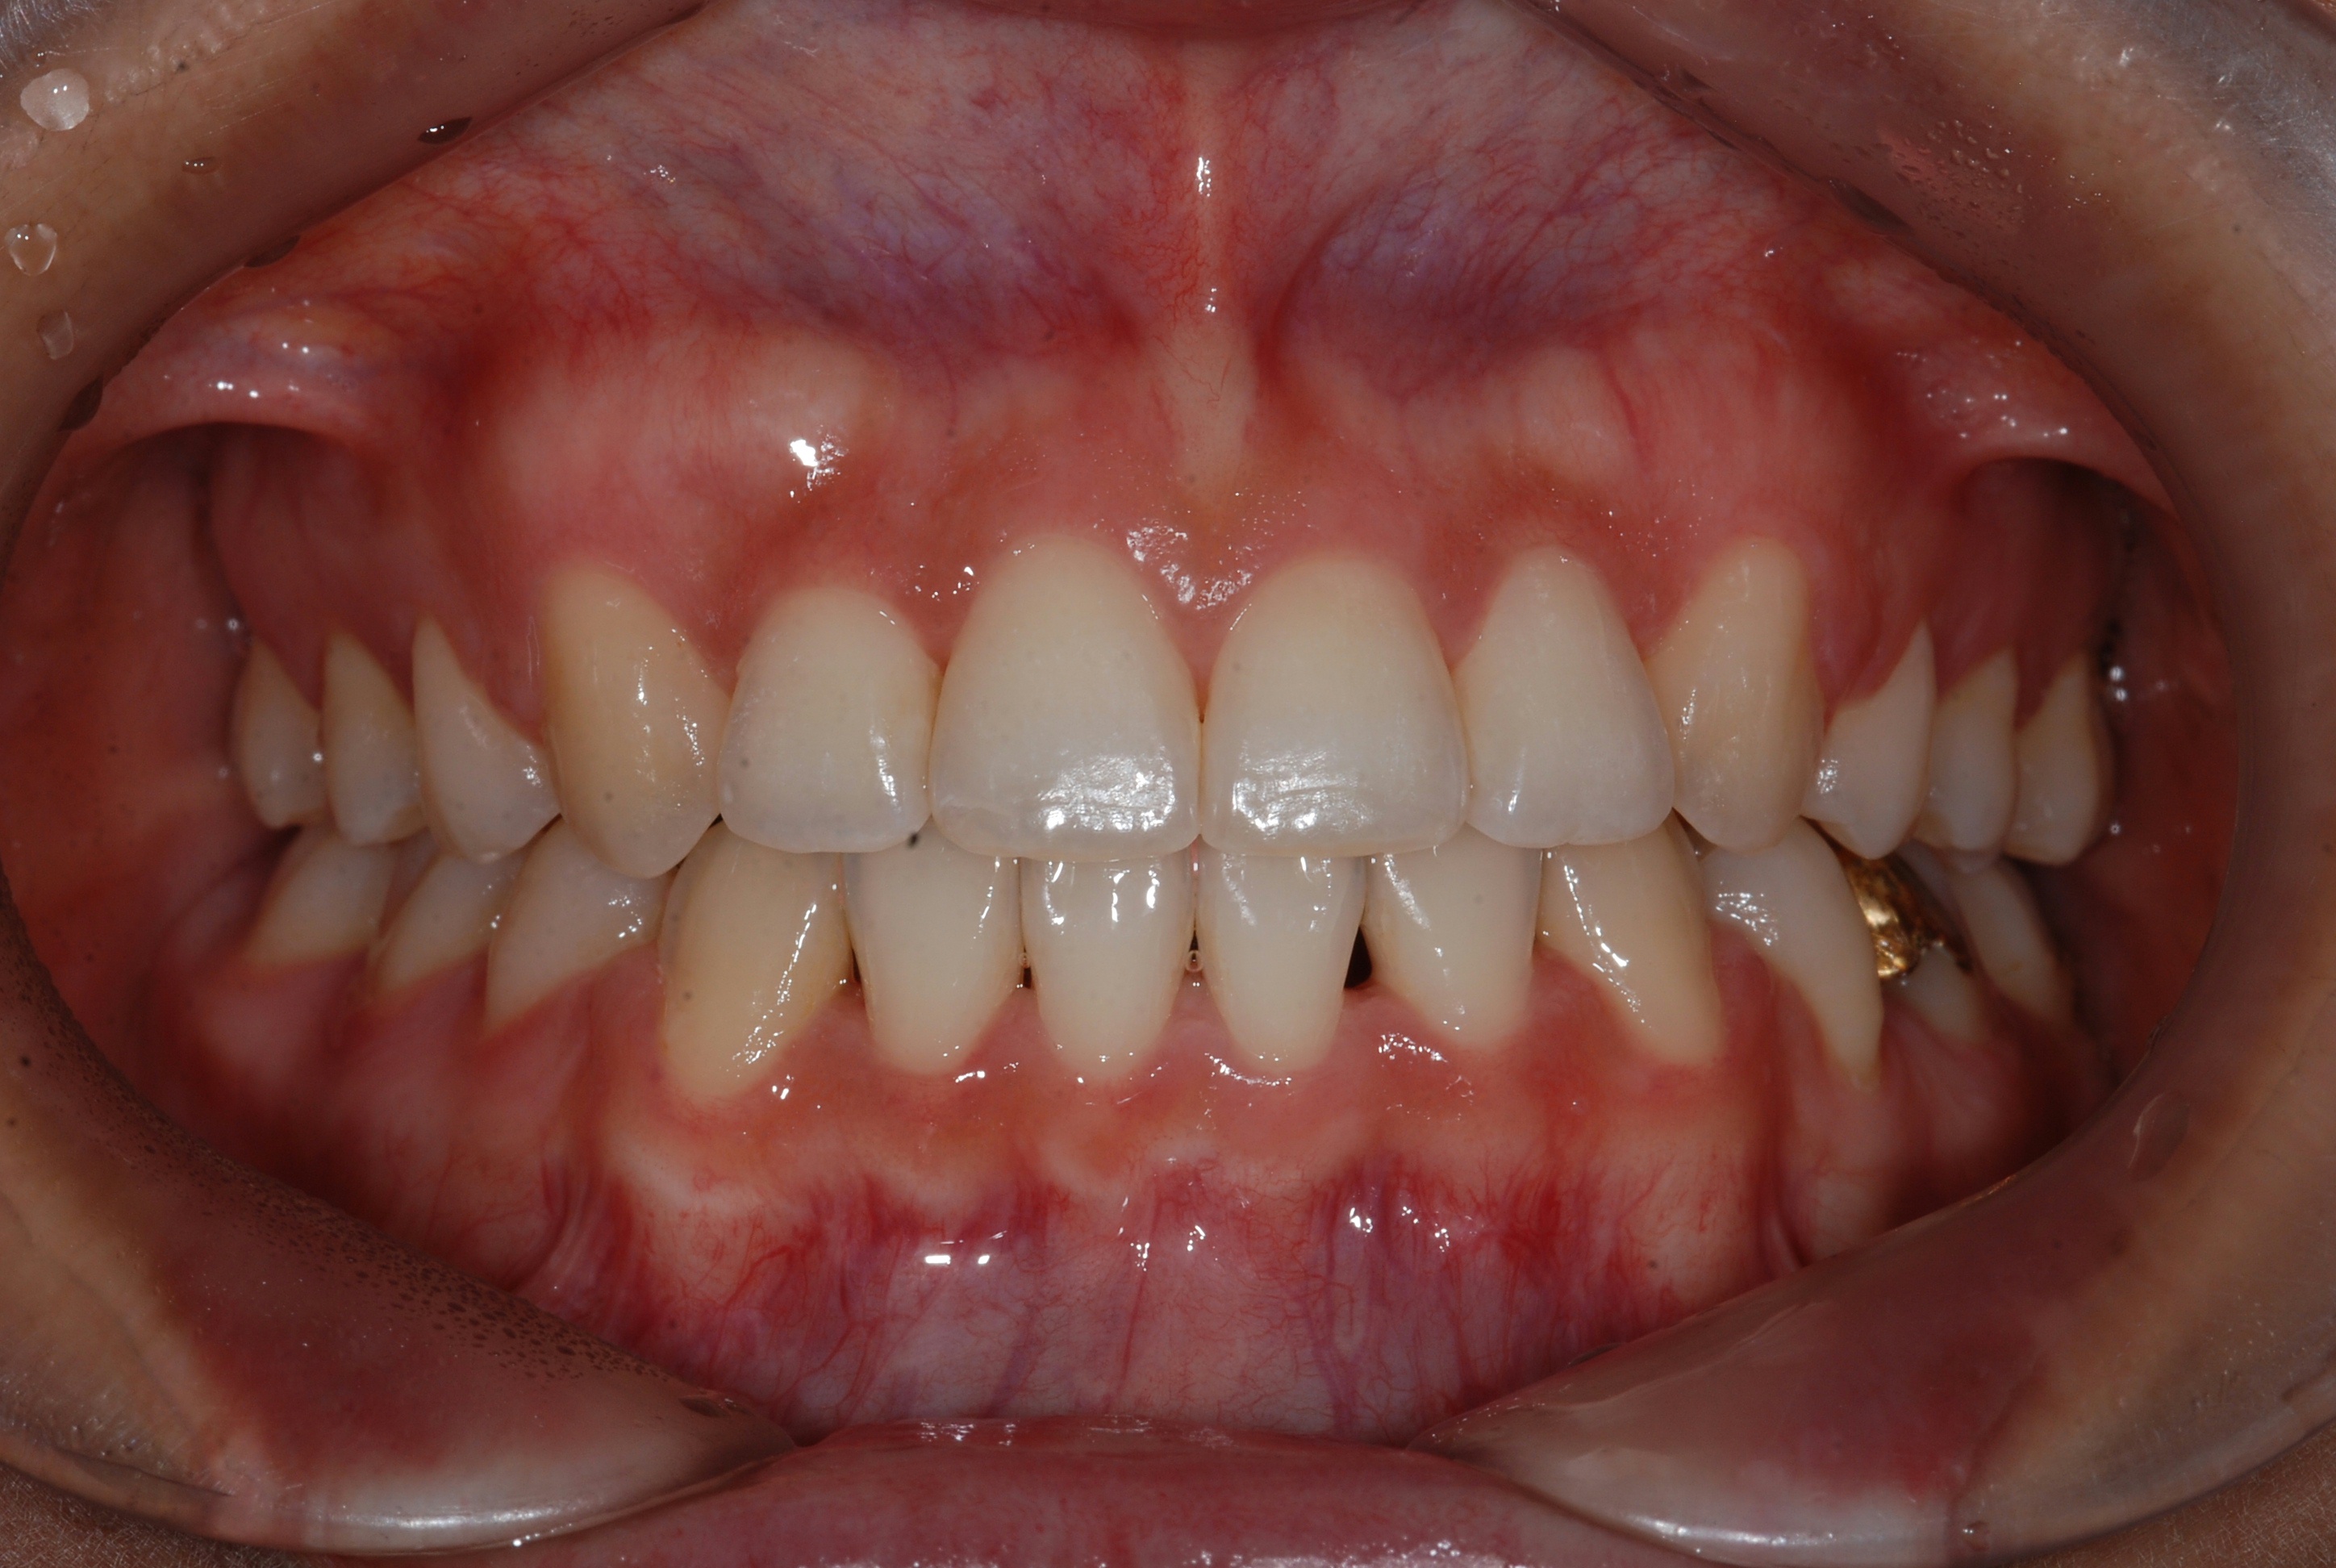

치료 전 사진입니다.